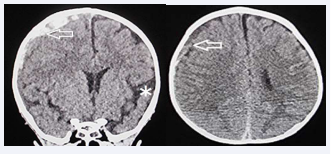

Post-operative CT showed decreased volume of acute subdural hematoma without brain swelling (Figure 2).

Figure 2 Computed tomography Post-op on the day. Left & Right (Axial View): Decreased volume of acute subdural hematoma on the right side. (arrows)

Figure 2: Computed tomography Post-op on the day.

Left & Right (Axial View): Decreased volume of acute subdural hematoma on the right side. (arrows)